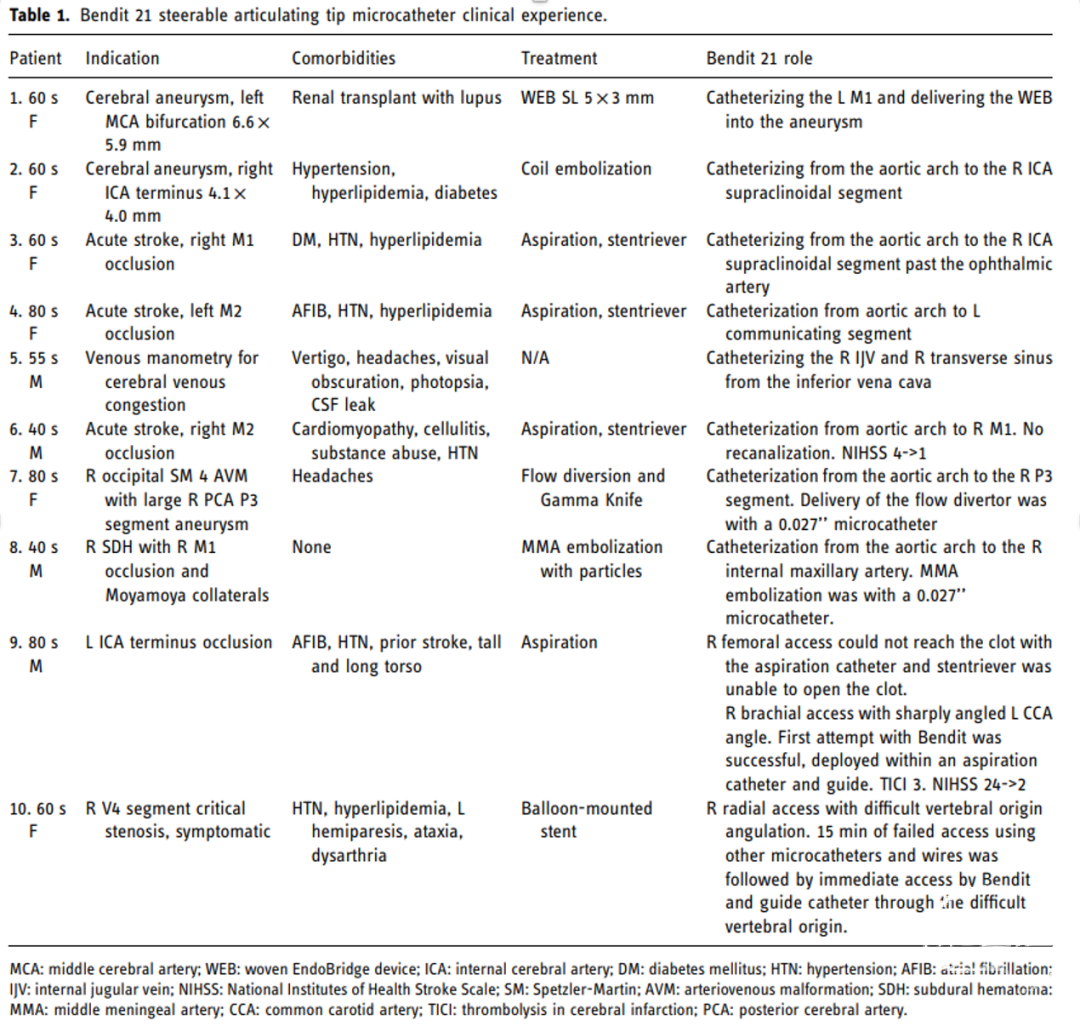

结果

病例集锦